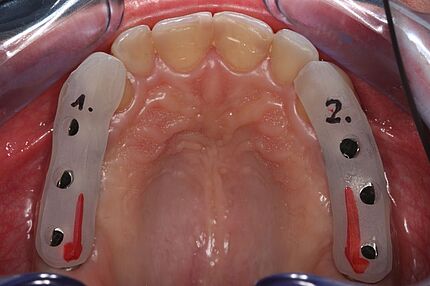

Im Journal Zahnmedizin up2date demonstrieren unsere Ästhetik-Spezialisten in einem weiteren Beitrag zum Thema professionelle Zahnaufhellung wie ein entsprechend angeleitetes At-Home-Bleaching funktioniert. Die entscheidende Vorbereitungsphase mit der Herstellung der Schienen und der adäquaten Instruktion des Patienten werden in dieser Publikation anhand eines Bildessays illustriert.